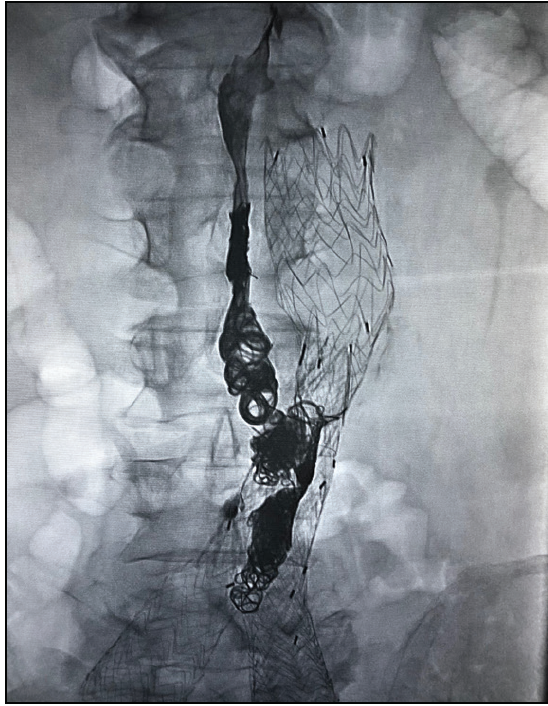

What Are Ruby Coils Made Of . The ruby® coil, pod® (penumbra occlusion device), and packing coil—all. The ruby coils were easily delivered through the microcatheter at a 180° angle. Although each of these products was designed for dedicated purposes, they can be used to complement each other ( figure 1 ). Indicated for arterial and venous. Penumbra’s embolization platform is made up of three unique detachable coil technologies:

The ruby coils were easily delivered through the microcatheter at a 180° angle. Penumbra’s embolization platform is made up of three unique detachable coil technologies: The ruby® coil, pod® (penumbra occlusion device), and packing coil—all. Indicated for arterial and venous. Although each of these products was designed for dedicated purposes, they can be used to complement each other ( figure 1 ).